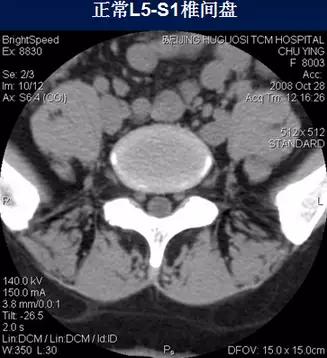

常规腰椎CT扫描层面

常规腰椎CT扫描L3-S1段,分为

(2)椎间盘层面(软组织窗):观察椎间盘、硬膜囊、神经根、韧带等软组织。

二、椎间盘膨出

椎间盘影均匀超出相应椎体边缘,轻度时CT表现为间盘后缘正常肾形凹陷消失,圆隆饱满。